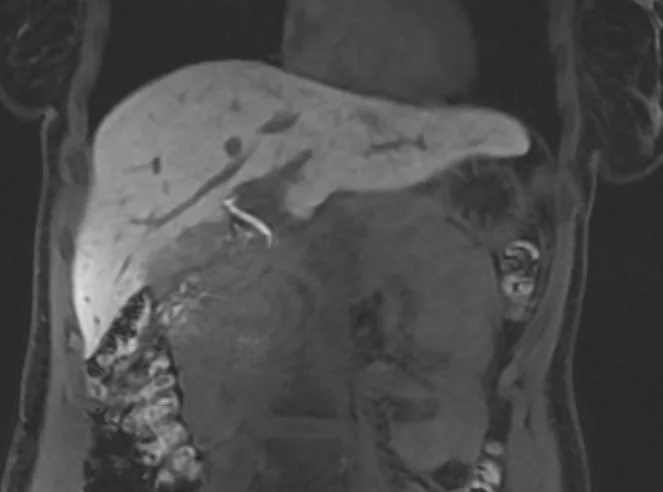

Eksempler på MR Scanninger

Denne højteknologiske metode er særligt velegnet til at visualisere det bløde væv i bughulen og kan afsløre selv mikroskopiske forandringer i levervævet. Scanningen giver et holistisk billede af hele leverregionen inklusive galdeblære, bugspytkirtel og galdegange.

For optimal diagnostik anvender vi i særlige tilfælde et leverspecifikt kontrastmiddel, der markant forbedrer muligheden for at differentiere mellem normalt levervæv og potentielle sygdomsforandringer.